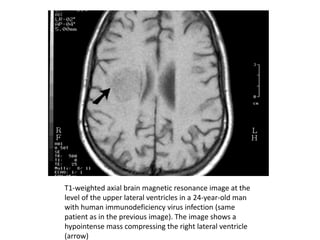

T1-weighted axial brain magnetic resonance image at the

level of the upper lateral ventricles in a 24-year-old man

with human immunodeficiency virus infection (same

patient as in the previous image). The image shows a

hypointense mass compressing the right lateral ventricle

(arrow)

Imaging • A brainCT scan or MRI with and without contrast is indicated for all patients presenting with altered mental status, headaches, seizures, or focal neurologic signs. MRI clearly is the superior technique but is not available universally. • Single or multiple hypodense or hypointense lesions in white matter and basal ganglia with mass effects may be observed on CT or MRI scans. Lesions may enhance in a homogeneous or ring pattern with contrast (see the images below). Imaging studies may be normal in diffuse toxoplasmosis.

T1-weighted axial brainmagnetic resonance image at the level of the upper lateral ventricles in a 24-year-old man with human immunodeficiency virus infection (same patient as in the previous image). The image shows a hypointense mass compressing the right lateral ventricle (arrow)